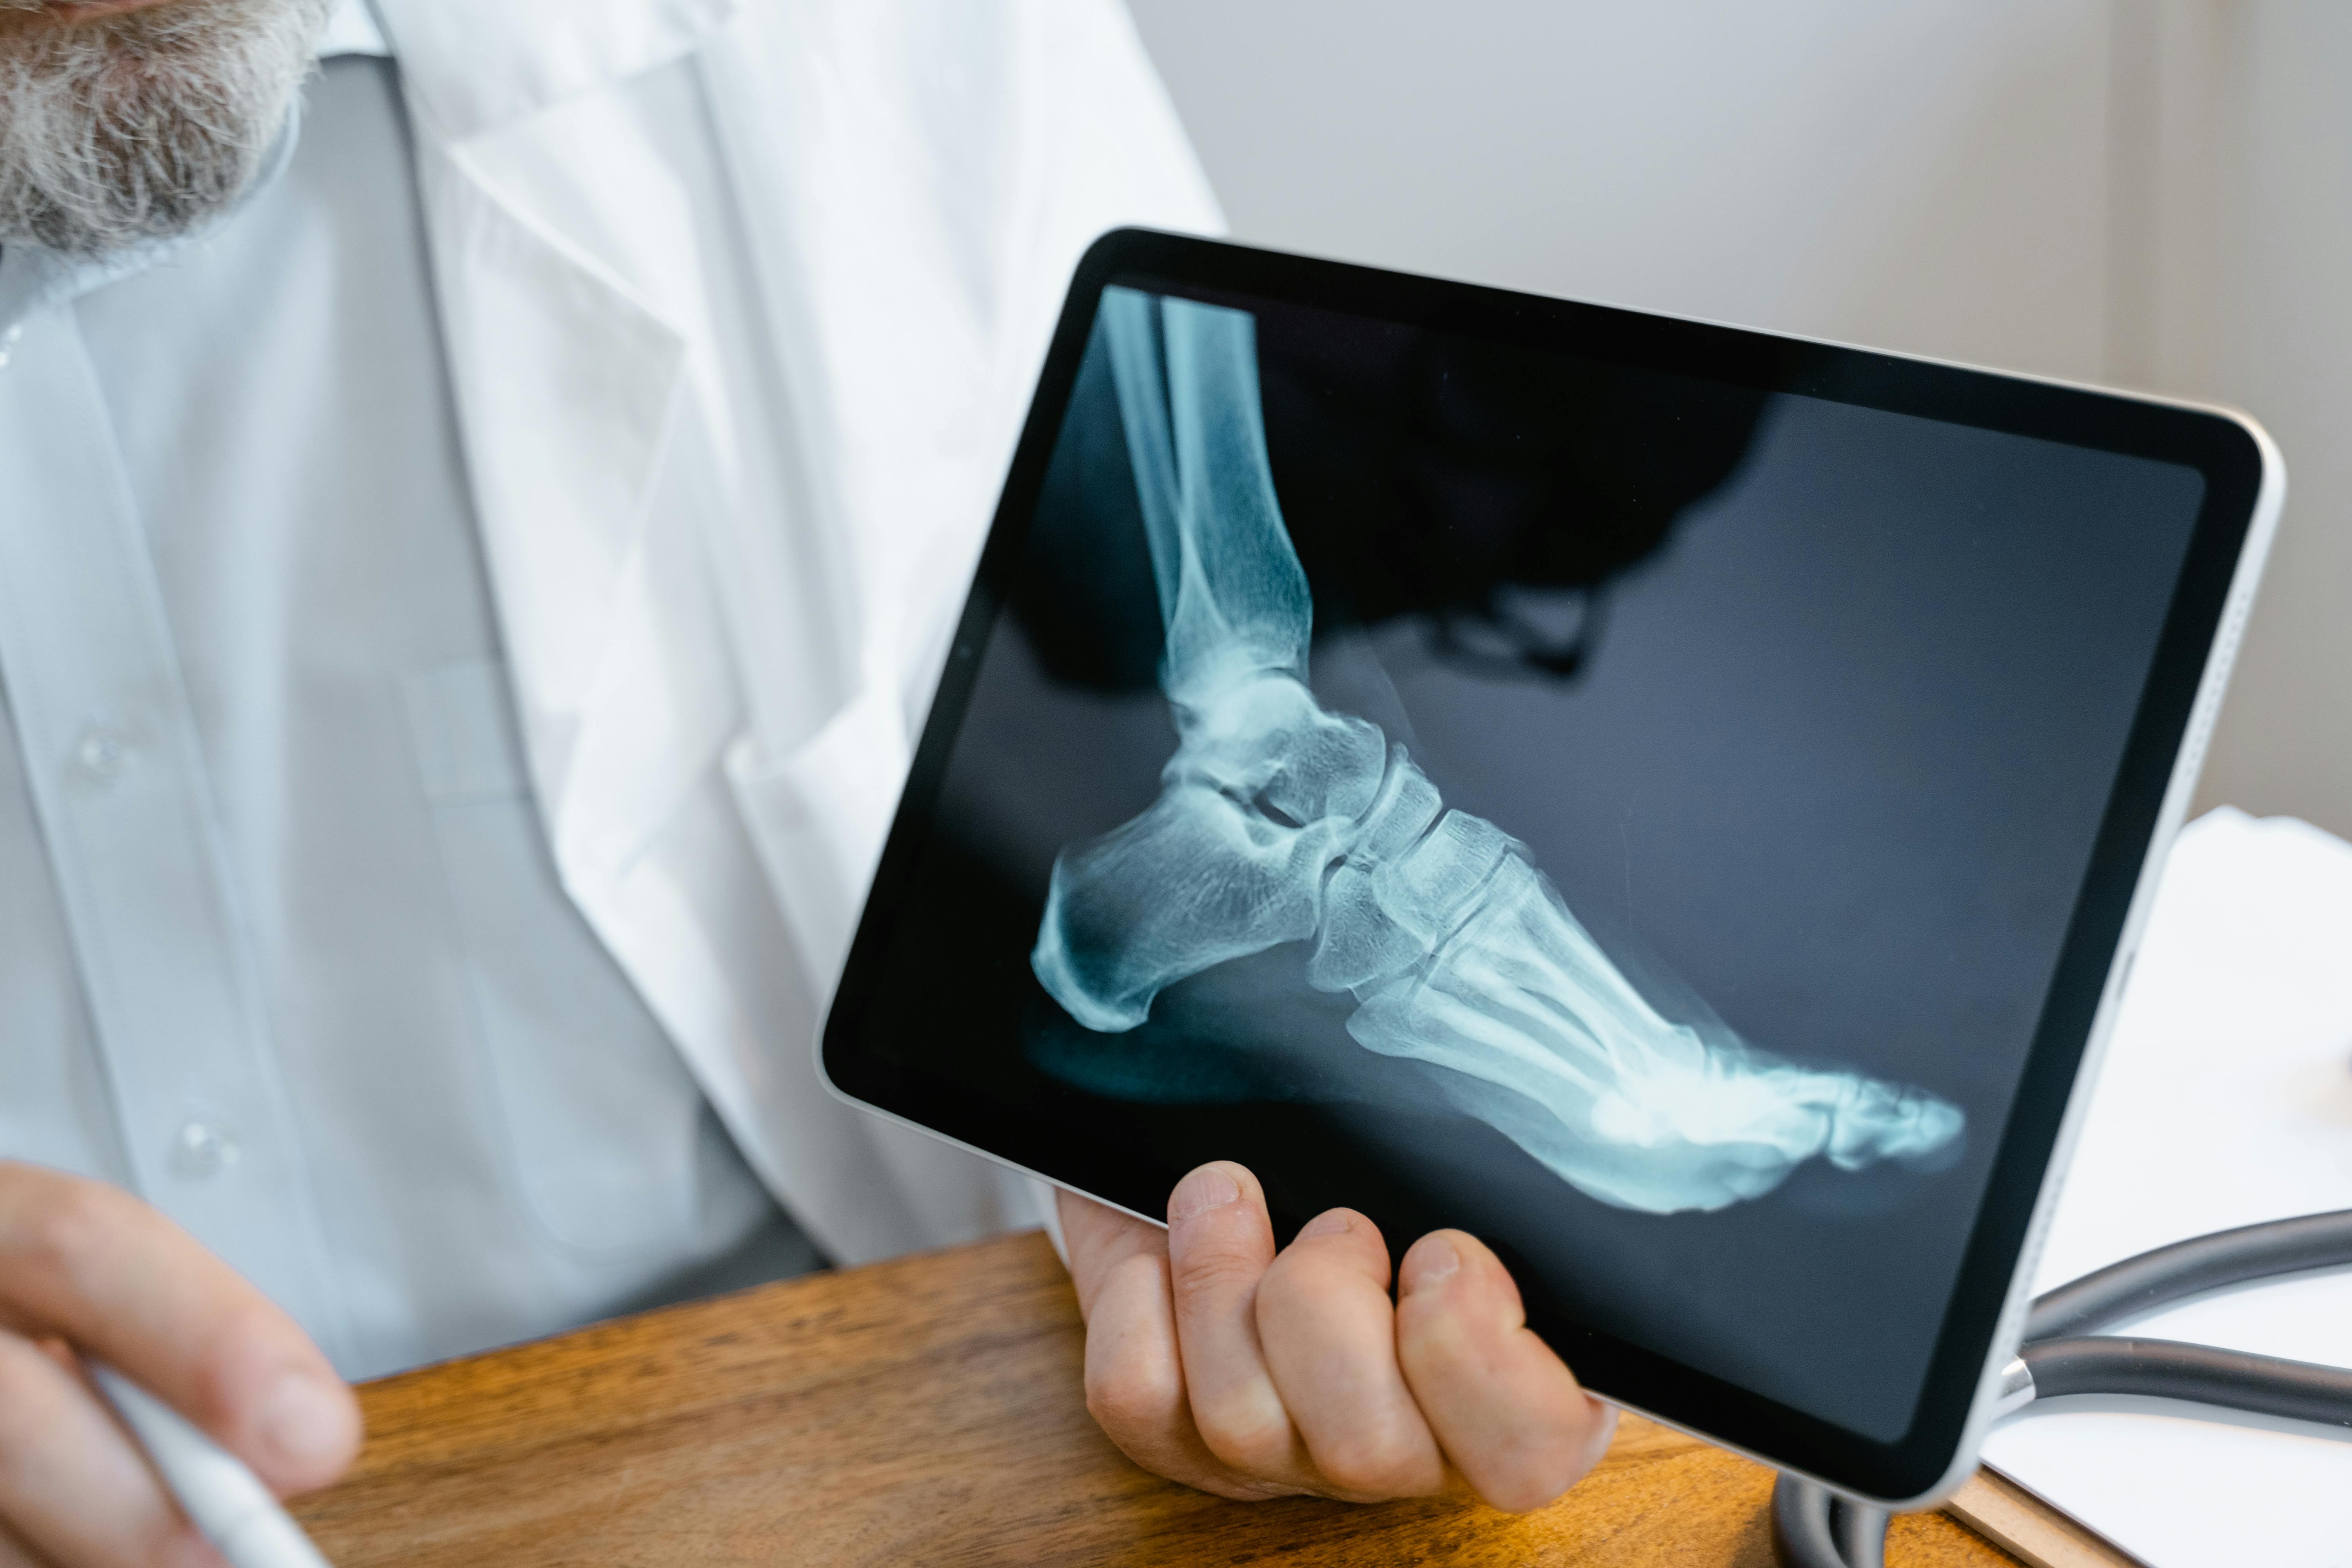

- Los tratamientos para la osteoporosis pueden incluir el uso de un anticuerpo monoclonal contra la pérdida ósea, que refuerza los huesos y reduce las posibilidades de fractura al dirigirse específicamente al Ligando del RANK (RANK-L), para regular los osteoclastos (células que degradan los huesos), conduciendo a una reducción en la resorción ósea y a un aumento en la masa ósea.

Este tipo de tratamiento está indicado para mujeres posterior a la menopausia, reduciendo la incidencia de fracturas de cadera, vertebrales y no vertebrales.

También está indicado para el tratamiento de la pérdida ósea en pacientes que se someten a ablación hormonal para cáncer de próstata o cáncer de mama, así como para pacientes con osteoporosis inducida por glucocorticoides.

Estudios han demostrado su eficacia en la reducción de fracturas de columna, cadera y no vertebrales, hasta en 68%, y se le ha asociado con reducción persistente del recambio óseo, aumentos continuos en la DMO y baja incidencia de fracturas.

Foto de Tima Miroshnichenko: https://www.pexels.com/es-es/foto/pie-resultado-huesos-radiografia-8376138/